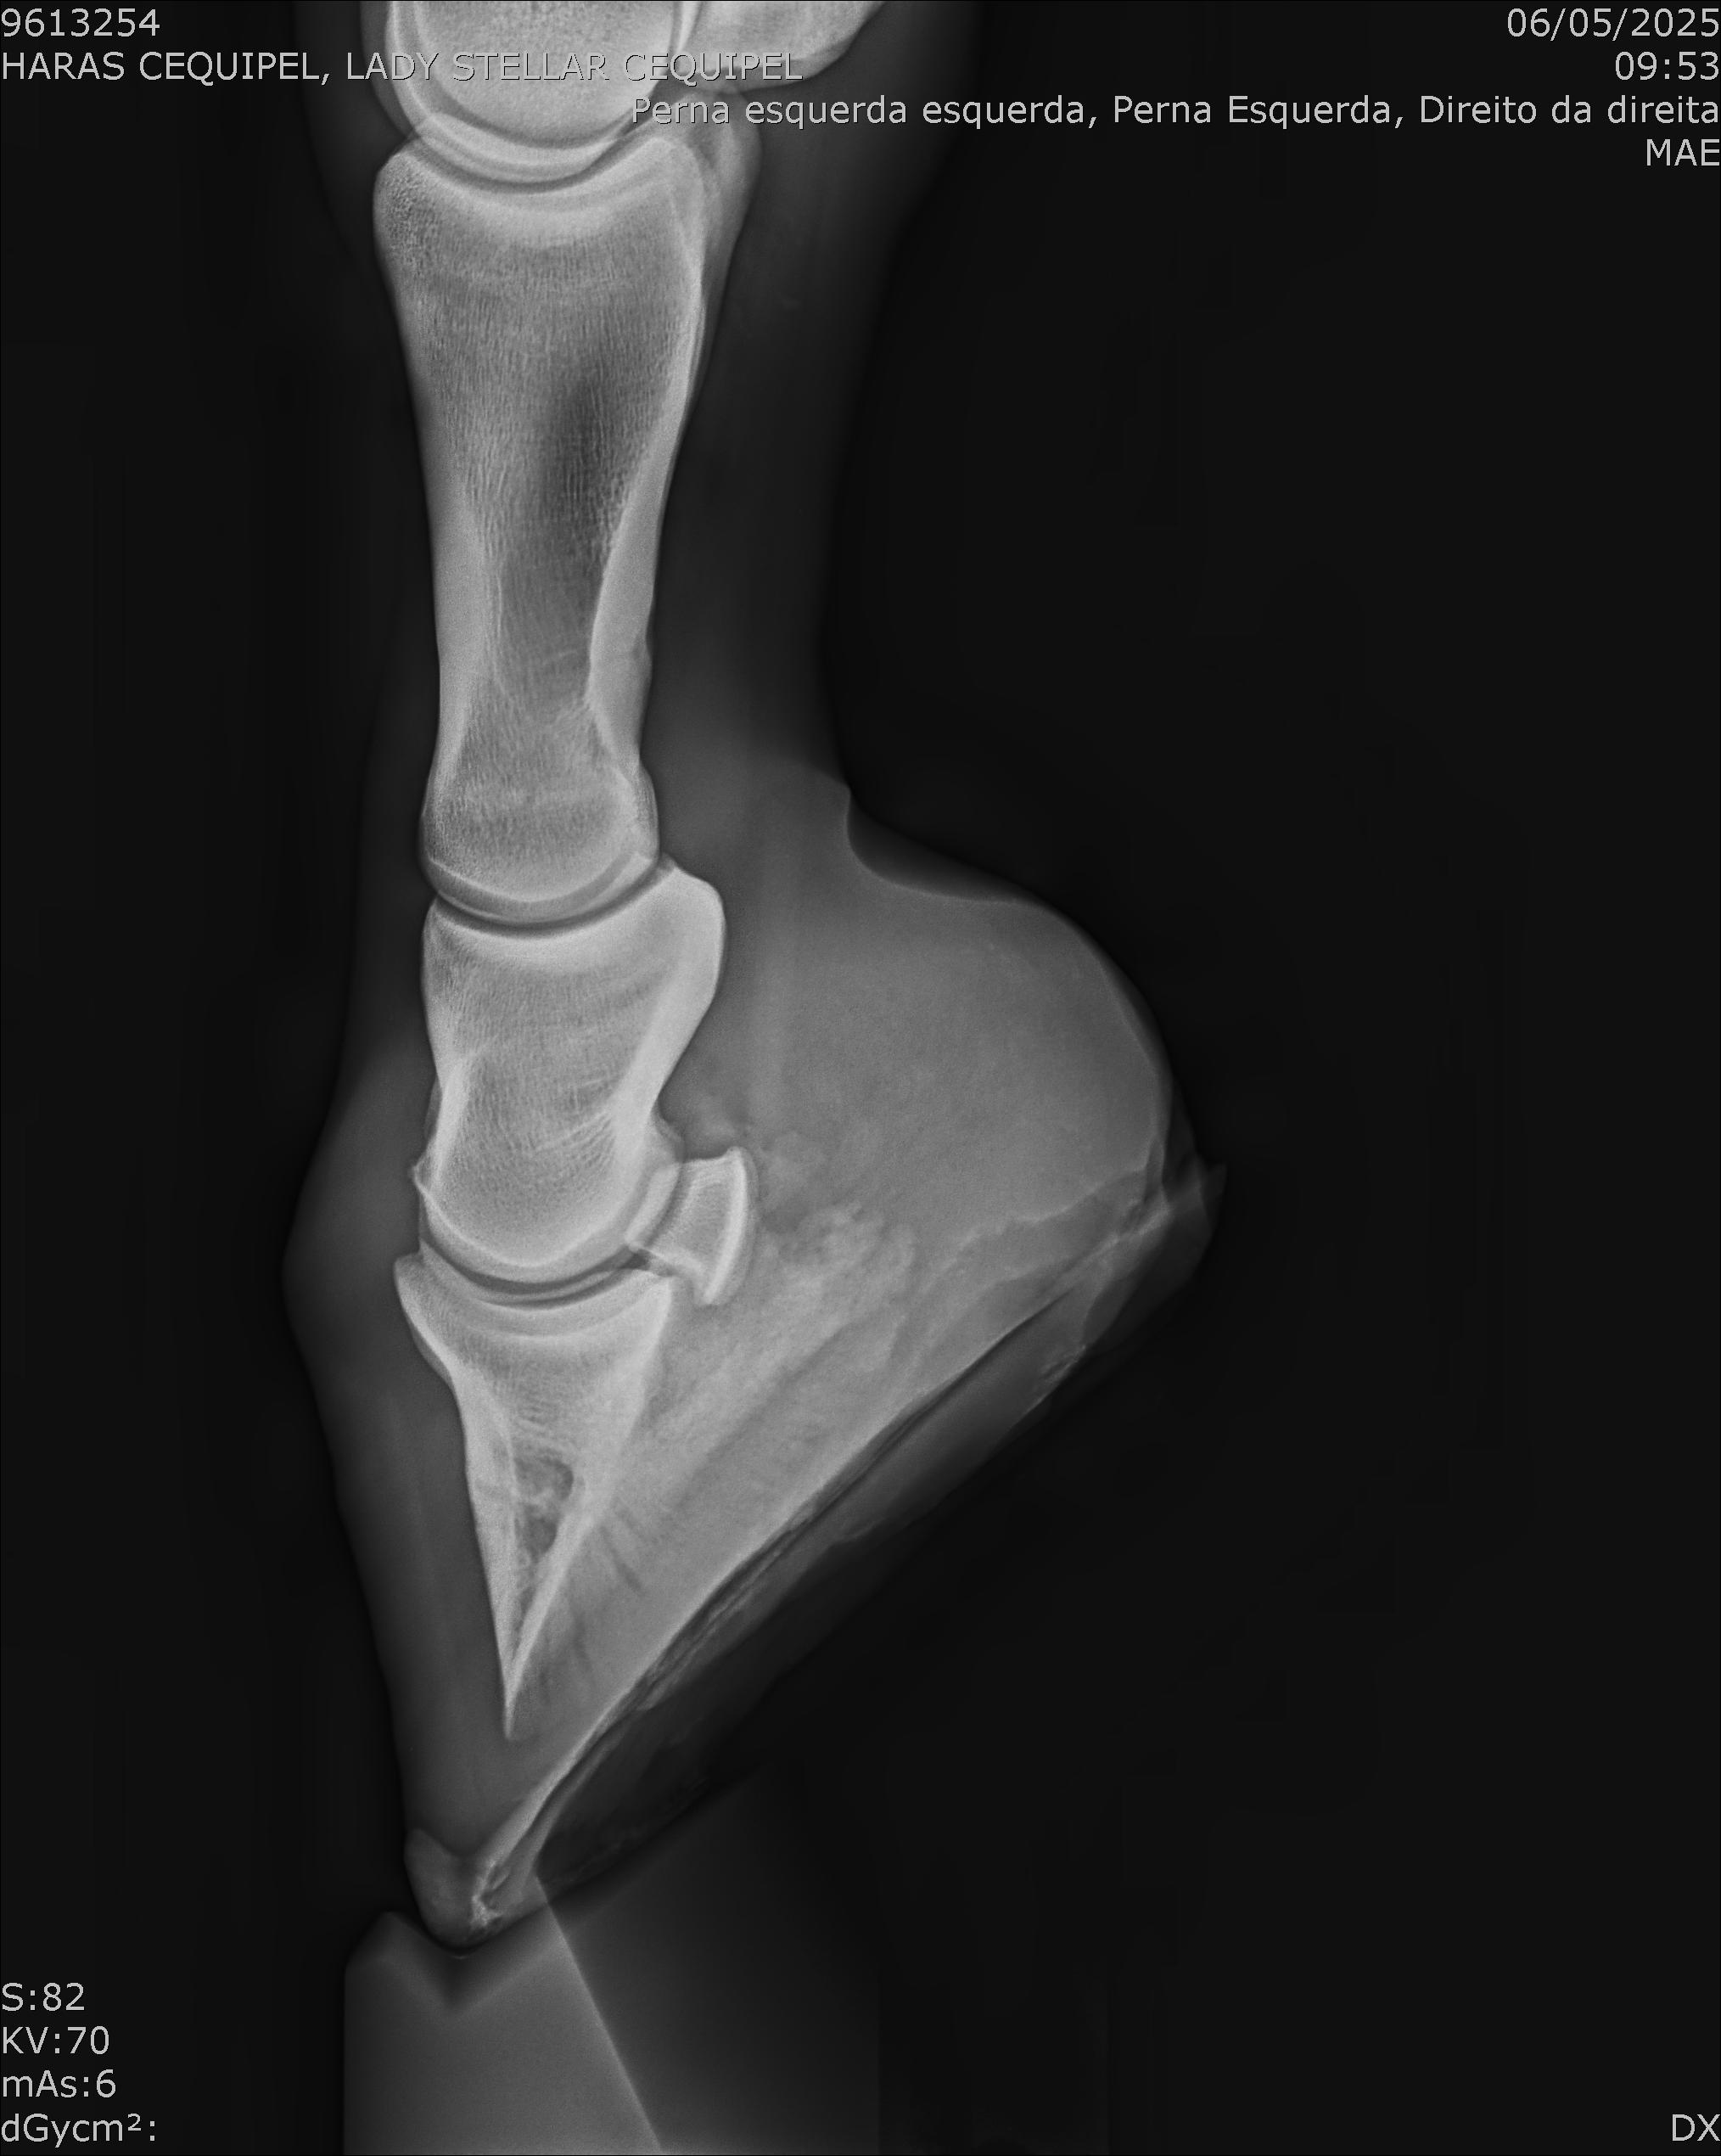

:: RAIOS-X DO LOTE